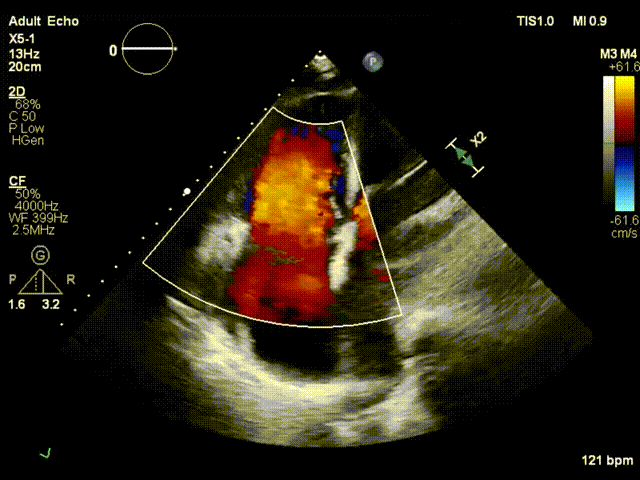

术前超声

术后超声